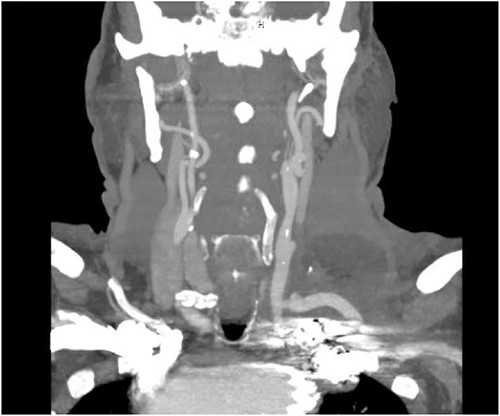

The patient is a 70-year-old male with an incidental finding of a proximal LSA aneurysm on computed tomography (CT) angiography of the chest performed for shortness of breath. He had no dysphagia, neurologic or vascular occlusive symptoms. He had no history of trauma or known congenital anomaly. The aneurysm had a maximal diameter of 3.4 cm and was located at the origin of the artery (Fig. 1). An aberrant left vertebral artery and hypoplastic right vertebral artery were also identified. The left vertebral artery originated from the aortic arch proximal to the LSA takeoff (Fig. 2) and provided dominant posterior cerebral circulation.

Preoperative CTA demonstrating aberrant left vertebral artery originating from the aortic arch, just proximal to the LSA.